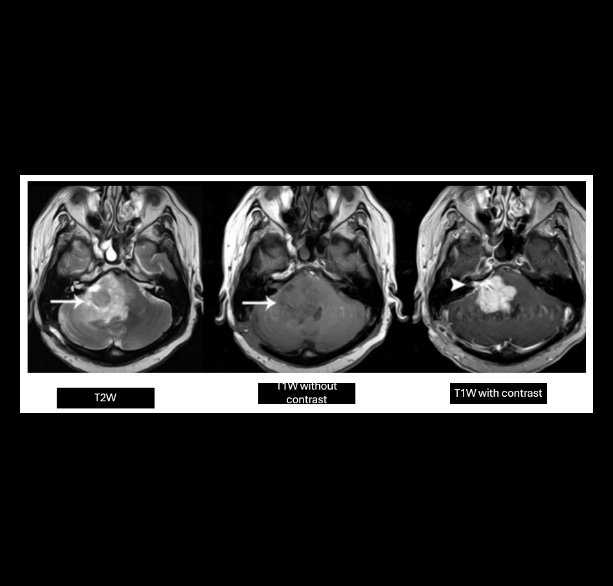

A 29-year-old man with alerted mental status. What is the most likely diagnosis?

- Glioblastoma

- Ependymoma

- Medulloblastoma

- Meningioma

- Schwannoma